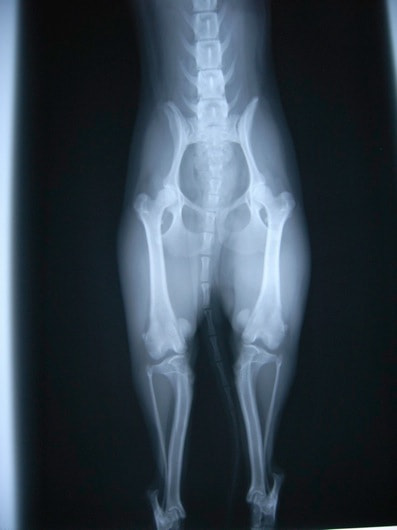

■ 症例20 ポメラニアン 8ヶ月 1.8kg

左右膝蓋骨脱臼 グレードⅢ

2ヶ月前から間欠的跛行が認められ、両膝の膝蓋骨脱臼整復術を行った。

手技は縫工筋及び内側広筋の解放、脛骨粗面の外側転位、滑車ブロック形造溝術、内外側関節包の縫縮を選択し実施した。

右側の膝蓋骨脱臼は上記手技で整復されたものの、左側はそれのみでは膝蓋骨が浮く様子が認められた。その為、PDS縫合糸にて膝蓋靱帯を1糸のみ縫合し、靱帯の縫縮を行った。